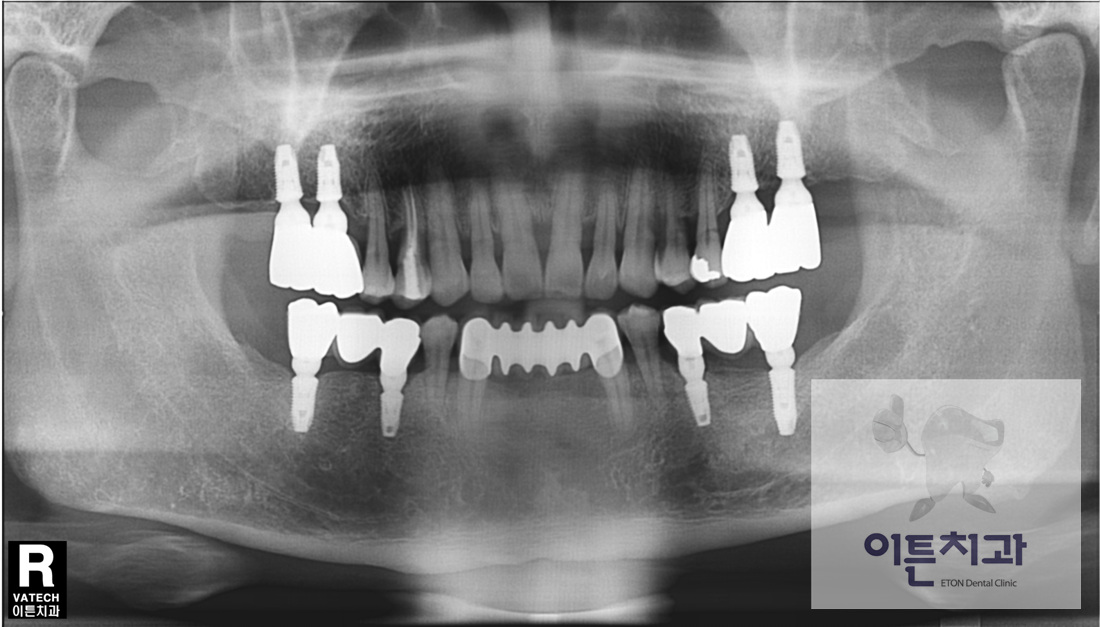

ÀÌ ÄÉÀ̽º´Â ÇÏ¾Ç ÀüÄ¡ºÎ´Â ºê¸´Áö, »óÇÏ¾Ç ±¸Ä¡ºÎ´Â ÀÓÇöõÆ®¸¦ ÀÌ¿ëÇÏ¿© ¼º°øÀûÀÎ °á°ú¸¦ ¾òÀº °æ¿ìÀÔ´Ï´Ù.

Ä¡¾Æ »ó½Ç ºÎÀ§¸¦ ¼öº¹ÇÏ´Â ¹æ¹ýÀº ¿©·¯°¡Áö°¡ ÀÖÀ¸¸ç ´ëÇ¥ÀûÀ¸·Î ºê¸´Áö¿Í ÀÓÇöõÆ®°¡ ÀÖ½À´Ï´Ù.

ºê¸´Áö´Â ¾çÃøÀÇ Æ°Æ°ÇÑ Ä¡¾Æ¸¦ Å©¶ó¿îÀ¸·Î ¾º¿ì¸é¼ Áß°£¿¡ ÀΰøÄ¡¸¦ ¸Å´Ù´Â ¹æ¹ýÀ̸ç

ÀÓÇöõÆ®´Â ÀΰøÄ¡±ÙÀ» »À¿¡ ½Ä¸³ÇÏ°í »óºÎ¿¡ ÀΰøÄ¡¸¦ ¿¬°á½ÃŰ´Â ¹æ¹ýÀÔ´Ï´Ù.